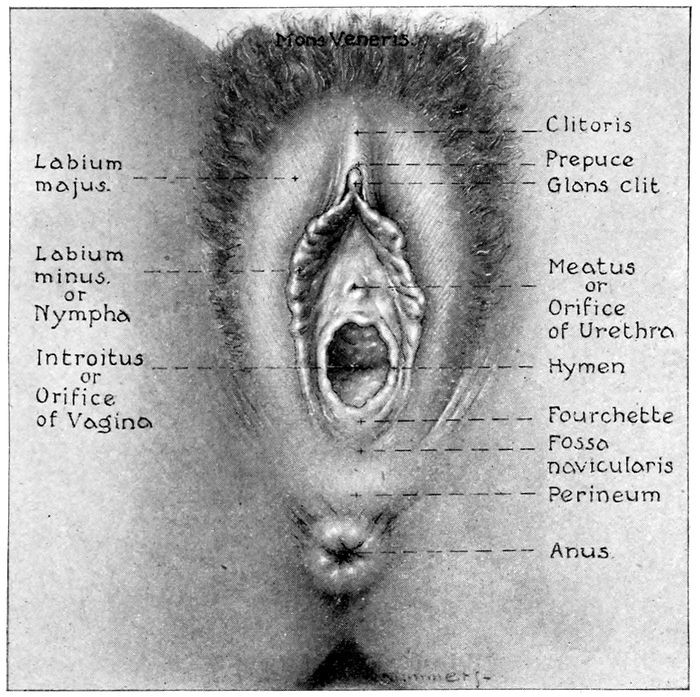

Fig. 6.—The external genitals. (Redrawn from Gray.)

The Mons Veneris.—The mons veneris is a gently

The Labia Majora.—The labia majora are the large

The Labia Minora.—The labia minora, or nymphæ,

The Clitoris.—The clitoris is an erectile structure analogous

The Vestibule.—The vestibule is bounded by the clitoris

The Hymen.—The hymen is a thin fold of membrane